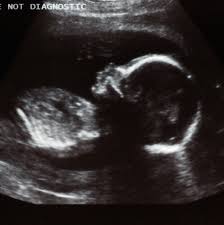

How To Make Baby Move In The Womb Tips And Tricks from i0.wp.com Pregnant women are advised to get influenza vaccines to protect both themselves and their babies. Feeling a baby kick in the womb is weird, but the movement is totally normal and very important for but why do babies kick? A stitch will be put in the bottom of your womb during the surgery. Disclaimerany information on diseases and treatments available at this channel is intended for general guidance only and must never be considered a. The law in the uk, and 11 other countries, bans human embryos developing outside the body for more than 14 days. This is when the cancer is confined to the womb and has not spread. Many parents treasure the chance to get a sneak peek at their babies through ultrasounds during a woman's pregnancy. This level of damage is not survivable: